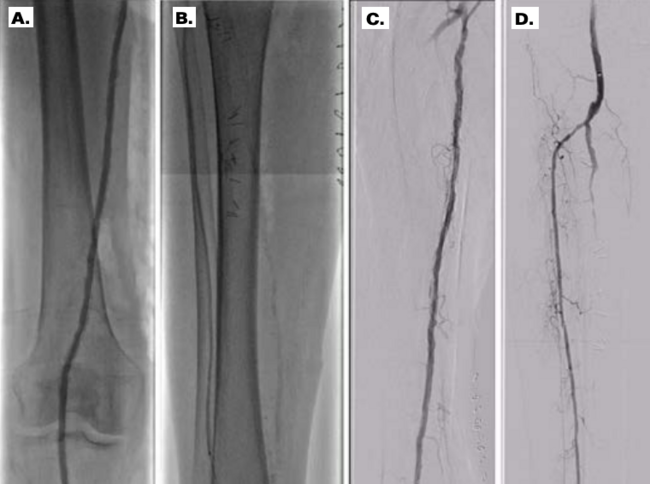

A 93-year-old woman with history of hypertension, permanent atrial fibrillation, prior cigarette smoking, chronic stage 3 kidney disease, and moderate aortic stenosis, presented to an outside hospital with disabling rest pain, discoloration and swelling of her right lower extremity. Physical examination revealed pale and cool right foot, absent dorsalis pedis and faint posterior tibial pulses, and gangrenous changes involving her second and third toes (Figure 1A). An urgent peripheral angiogram showed severely calcified, diffusely diseased superficial femoral artery (SFA) with CTO in the mid SFA segment, a second CTO in the distal popliteal artery, an occluded peroneal artery, densely calcified and diffusely diseased anterior tibial artery, and a patent but calcified posterior tibial artery with minimal antegrade flow.

An endovascular treatment strategy was attempted; however, the procedure was unsuccessful after multiple crossing attempts to penetrate the proximal calcified CTO had failed. The patient was evaluated by the vascular surgery team and, two days later, she was taken to the operating room for femoral-tibial bypass surgery. However, given dense calcifications in the vessel, attempts to place distal anastomosis were unsuccessful. Furthermore, vessel closure with a Prolene suture were unsuccessful with persistent bleeding, thus the posterior tibial artery was subsequently ligated proximally with a silk suture and the surgical site closed (Figure 1B). She was then transferred to our facility for a second opinion.

The patient was evaluated and a shared decision was made to proceed with a repeat intervention attempt to revascularize her leg in an attempt to prevent amputation and relieve her symptoms. She was promptly taken to the catheterization laboratory. Antegrade access was obtained under ultrasound guidance using a micropuncture access set (Cook Medical), and up-sized for a 6Fr x 10 cm Pinnacle sheath (Terumo Interventional Systems). Therapeutic anticoagulation was administered and activated clotting time (ACT) was maintained at more than 200 seconds. Digital subtraction angiography of the right lower extremity with runoff was obtained (Figure 2).